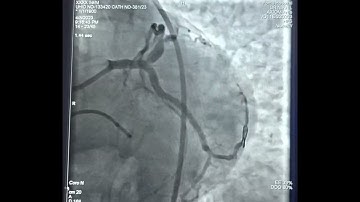

BICTO: Bifurcation and CTO/ LMCA-TAP stenting and LAD- CTO